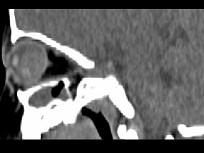

问题 男,2岁、右眼白瞳症1个月,CT影像如图,最可能的诊断为()

选项 A.眼球内寄生虫病 B.永存原始玻璃体增生症 C.脉络膜骨病 D.Coats病 E.视网膜母细胞瘤

答案 E